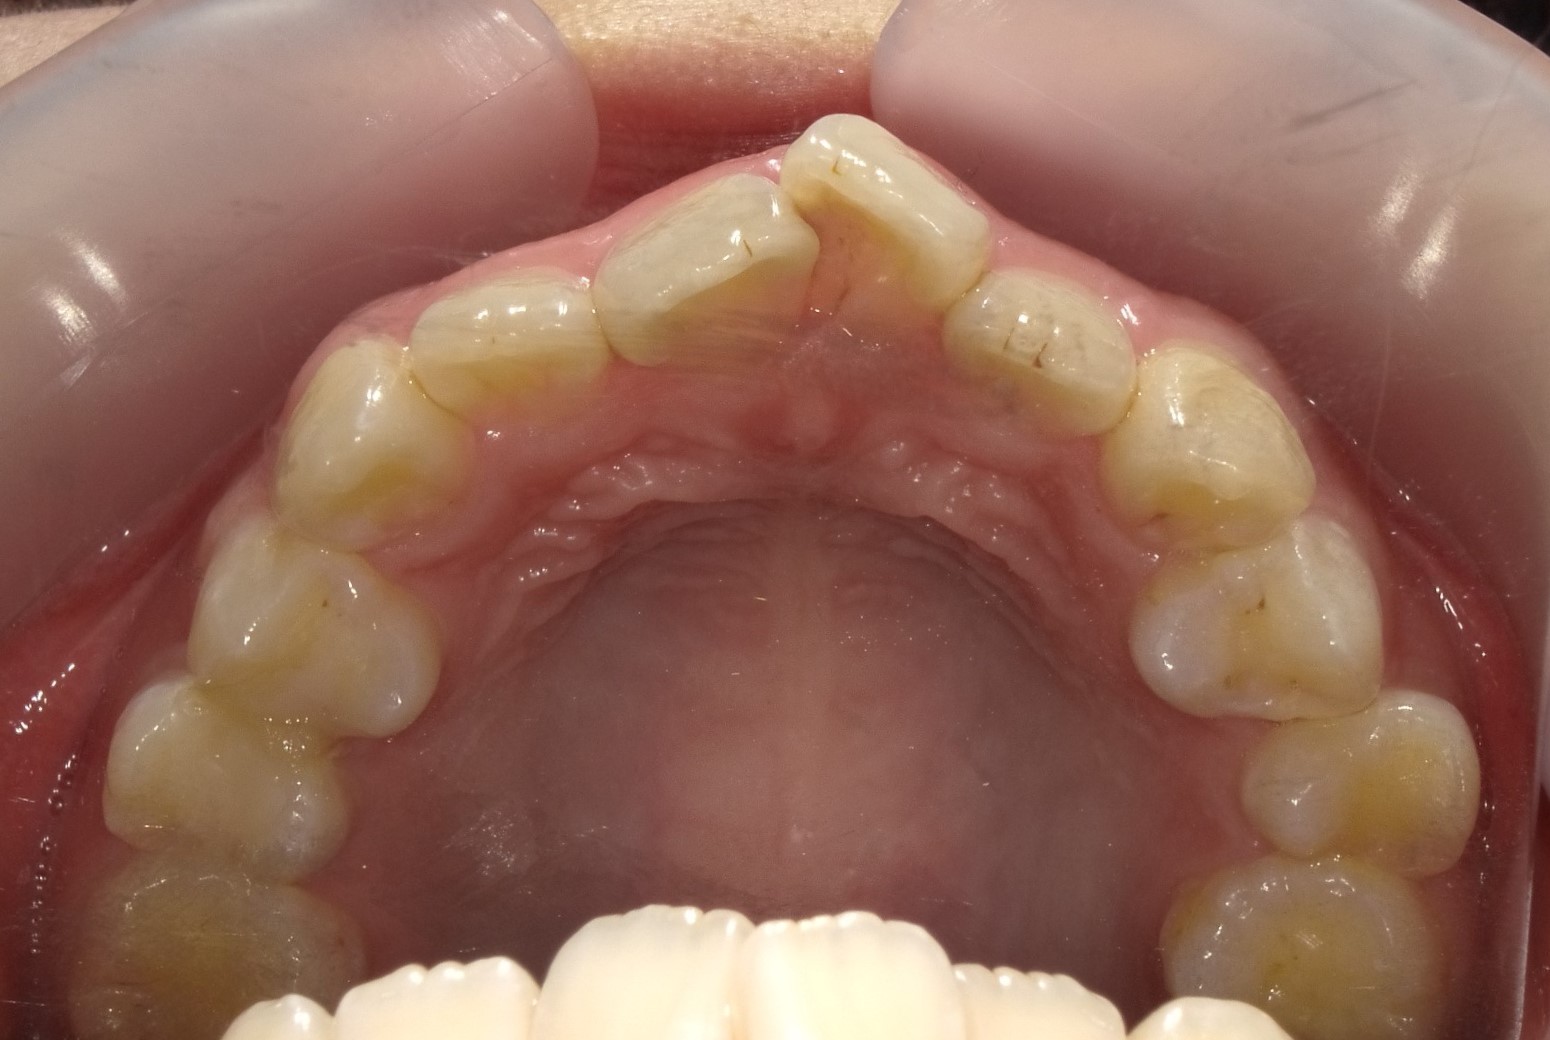

症例①|前歯の突出感(出っ歯)と歯の重なりをインビザラインで改善した症例

前歯の突出感(出っ歯)と、下の歯の重なり(叢生)を併発していた状態を、インビザラインで治療したケースです。

■ 治療前の状態(Before)

治療前は上顎前歯の突出感が目立ち、前歯が前方に傾いている状態でした。

あわせて下顎の歯並びには重なり(叢生)も見られ、歯列全体のバランスが乱れていました。